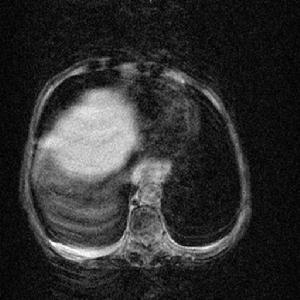

二、 多囊肝:囊腫大小不一,最大容量可達1000毫升以上,小者如芝麻、綠豆大小,囊腫散布全肝或某一肝葉,以右葉多見。大體切面呈蜂窩狀,囊腔內含澄清透明液體,不含膽汁。肝囊腫甚大時可壓迫肝細胞,致萎縮性變,可引起膽管狹窄,致膽囊炎,可引起肝功能損害,最後出現腹水、黃疸,甚至食道靜脈曲張。

人們所講的肝囊腫通常指非寄生蟲性肝囊腫。其真正的發病率尚不清楚,臨床上的病理有增多的趨勢,其原因與B超、CT等影象學診斷方法普及有關。肝囊腫中孤立性囊腫及多囊肝多見,孤立性肝囊腫通常無任何症狀,若囊腫較大可出壓迫症狀如腹痛,噁心,腹瀉等。囊腫的發生部位右肝居多。多發性肝囊腫又稱多囊肝,有半數上的病人合併有多囊腎,多囊肝常侵犯整肝臟。也有少數多囊肝病人的病變局限於肝臟的一葉或半肝範圍。